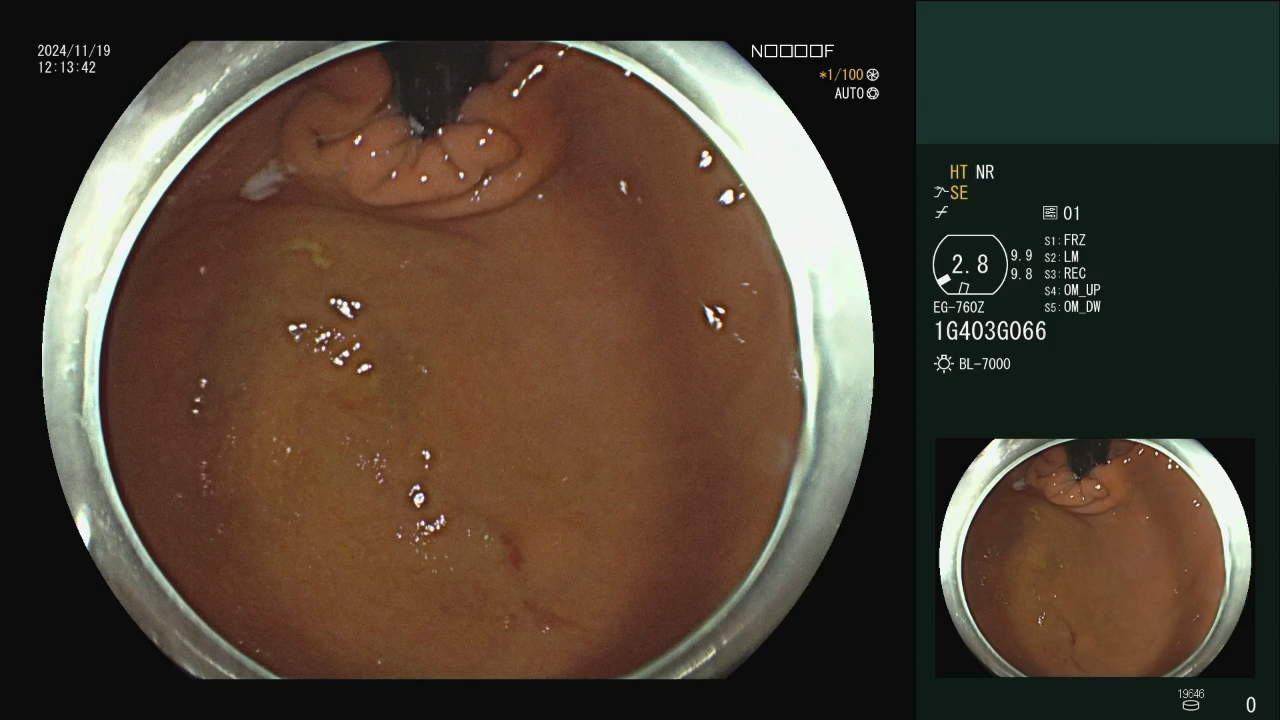

这个胃角病变你怎么诊断?

病例信息患者,女性,33岁,因腹胀一月余就诊,Hp阳性,奥林巴斯Hq290镜子,这个病变各位同仁考虑什么?